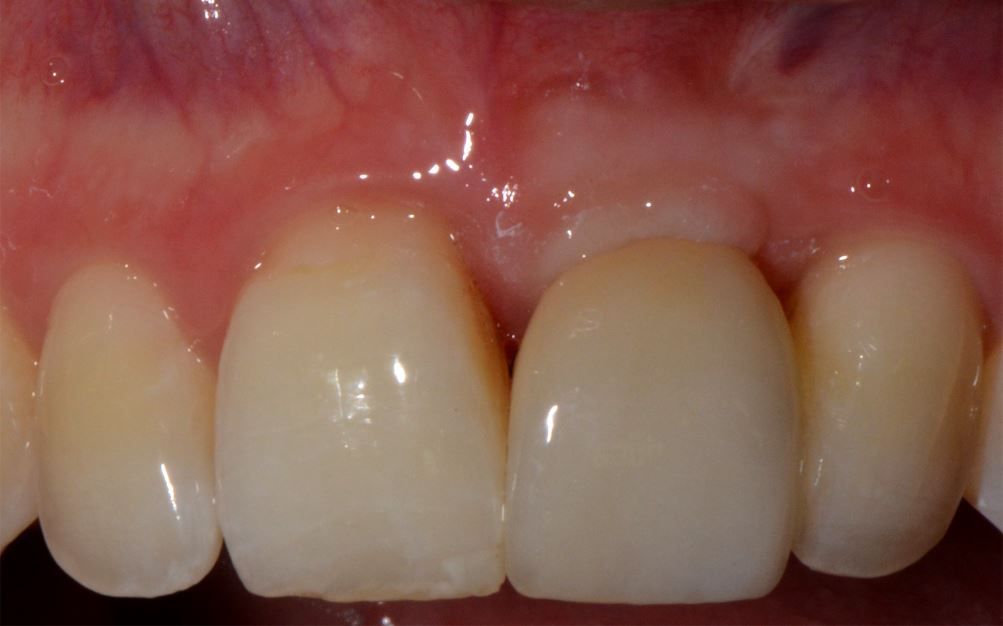

Abb. 3b

Situation direkt nach implantatprothetischer Versorgung (bei noch nicht abgeschlossener Weichgewebsregeneration) nach zuvor stattgefundener Zahnextraktion, Augmentation des Kieferkammbereiches und Spätimplantation.